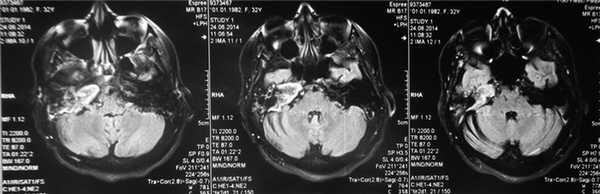

Пациентке была выполнена МРТ основания черепа по описанной методике (рис. 1). Рисунок 1. МРТ основания черепа больной Ф. с хроническим правосторонним гнойным средним отитом. Фистула лабиринта. Холестеатома. а — исследование в режиме Т1; б — в режиме Т2; в — в режиме non-EPI DWI.

В режиме Т1 справа определяется образование с низкой интенсивностью сигнала, а в режиме Т2 и non-EPI DWI — образование с гиперинтенсивным сигналом. Диагноз: хронический правосторонний гнойный средний отит; холестеатома; фистула лабиринта. Пациентка была подвергнута санирующей операции на правом ухе с тимпанопластикой и облитерацией паратимпанальных пространств. Были выявлены холестеатома, заполняющая аттик, адитус, антрум, деструкция цепи слуховых косточек, фистула латерального полукружного канала. Послеоперационный период протекал без особенностей, на 15-е сутки была удалена гемостатическая губка и силиконовая выстилка. При контрольном осмотре ухо сухое, отмечает улучшение слуха, головокружения нет. Через 12 мес проведено повторное МРТ-исследование. Признаков холестеатомы не обнаружено. Получен хороший функциональный результат — ухо толерантно к воде, самоочищается.